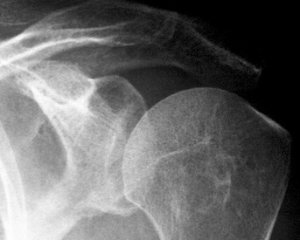

По степени тяжести артроз делится на четыре категории. Для их определения обычно проводится рентгенологическое обследование.

Для выставления окончательного диагноза необходимо проведение дополнительных методов исследования. При этом основным из них является рентгенологическое. С его помощью удается определить степени поражения плечевого сустава.

Чтобы обнаружить признаки артроза плечевого сустава, выполняют рентгенографию в двух проекциях, которая позволяет оценить степень сужения суставной щели, состояние поверхностей костей, величину и количество остеофитов, наличие жидкости, воспаления окружающих тканей.